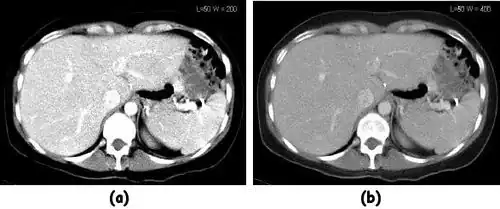

![]() |

- Examples of image display manipulation are shown in the two figures above. In Figure 7.15.2, the same image of a slice through a patient's liver is displayed using a relatively narrow window (high contrast) and also with a wide window. The image with the narrower window appears noisier, but this is merely a reflection of the fact that the gray scale is spread over a narrow range of CT-numbers.

- Figure 7.15.3 illustrates the use of a relatively narrow window to highlight pathology in the lungs.